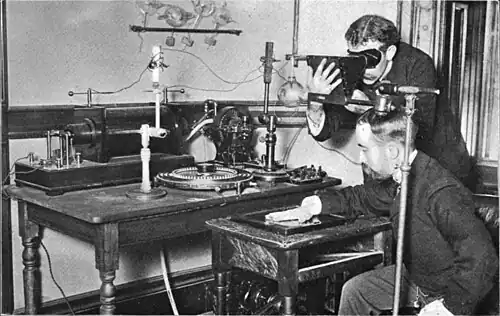

История рентгенологии начинается в 1895 году, когда Вильгельм Конрад Рентген впервые зарегистрировал затемнение фотопластинки под действием рентгеновского излучения. Им же было обнаружено, что при прохождении рентгеновских лучей через ткани кисти на фотопластинке формируется изображение костного скелета (см. Рука с кольцами). Это открытие стало первым в мире методом медицинской визуализации, до этого нельзя было прижизненно, не инвазивно получить изображение органов и тканей. Рентгенография очень быстро распространилась по всему миру. В 1896 году в России был сделан первый рентгеновский снимок[1].

В 1918 году в России была создана первая рентгенологическая клиника. Рентгенография используется для диагностики всё большего числа заболеваний. Активно развивается рентгенография лёгких. В 1921 году в Петрограде был открыт первый рентген стоматологический кабинет. Активно ведутся исследования, совершенствуются рентгеновские аппараты. Советское правительство выделяет средства на развёртывание производства рентгеновского оборудования в России. Рентгенология и производство оборудования выходят на мировой уровень[2].